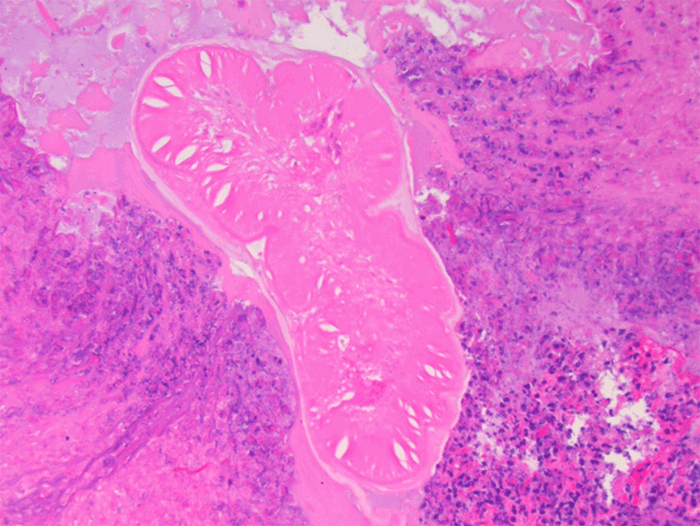

The patient recovered from the operation without complication and was discharged home on postoperative day two. Microscopic review of the adhesive bands removed during the procedure were notable for fibro-inflammatory reaction surrounding necrotic parasites nematodal in morphology and most consistent with anisakis (Figure 3). The patient was evaluated by an infectious disease specialist and treated with a one-time dose of oral 400 mg albendazole. He was seen for follow-up in the surgical clinic on postoperative 16 and was recovering well from his procedure without further gastrointestinal issues.

Figure 3. Microscopic slides from surgically excised intra-abdominal adhesions showing fibrosis, inflammation, and hemorrhage surrounding a necrotic, nematode parasite.